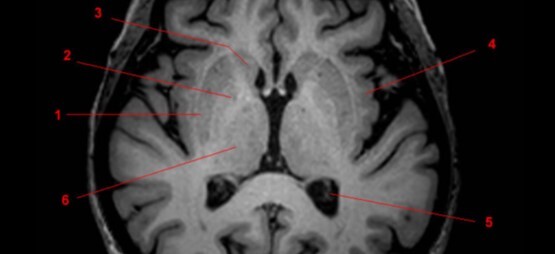

Label 1-6

A

1. Rt lateral ventricle

2. Lt caudate nucleus

3. Lt putamen

4. Lt globus pallidus

5. Rt temporal lobe

6. Rt Sylvian fissure